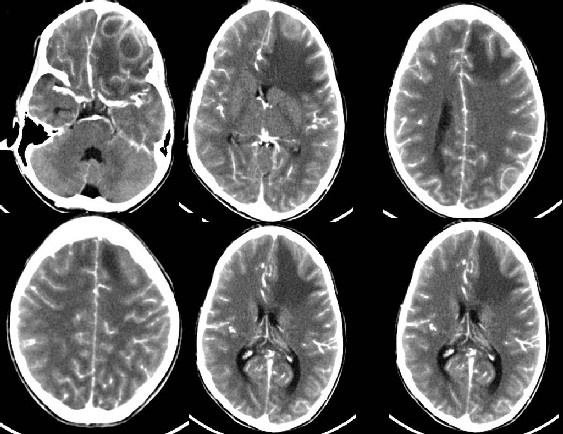

Áp xe não. Nguồn: Pedsradiology. |

Vài ngày sau, kết quả xét nghiệm dịch lấy từ khối áp xe được gửi đến. Hóa ra ổ bệnh trong não Carla là do vi khuẩn Streptococcus milleri gây ra. Đây vốn là loại vi khuẩn thường thấy trong miệng và hệ tiêu hóa. Nhưng trong trường hợp của Carla, vi khuẩn này lại xâm chiếm não bộ. Để chống lại sự nhiễm khuẩn, cơ thể đã sản sinh ra các tế bào bạch cầu. Các tế bào miễn dịch đã chết và chất bẩn kết hợp lại tạo thành ổ áp xe. Ổ áp xe này đè lên não, đe dọa mạng sống của Carla.